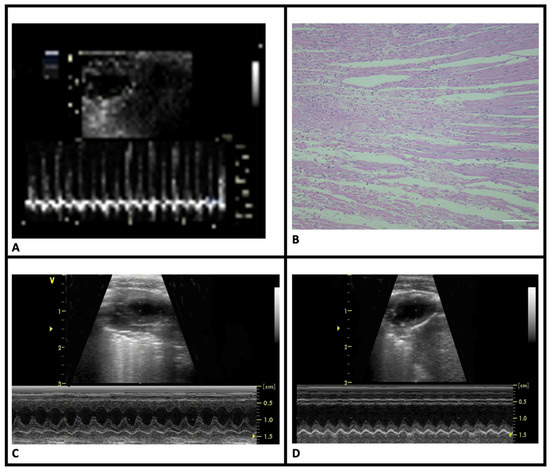

Chronic kidney disease (CKD) affects nearly 850 million people worldwide, and most patients with kidney failure are treated with kidney replacement therapy. Despite technological progress, venous congestion remains a major determinant of morbidity and mortality, and is often underdetected by conventional tools such as clinical evaluation, weight changes, blood pressure measurement, or bioimpedance. Point-of-care ultrasonography (PoCUS) has transformed this diagnostic landscape by providing real-time, physiology-based insights into both left- and right-sided filling pressures. In dialysis care, multiple or confluent B-lines and subtle pleural irregularities suggest elevated pulmonary capillary wedge pressure, while a dilated inferior vena cava (IVC) with reduced collapsibility and increased portal vein pulsatility indicate elevated right atrial pressures. Integrating these sonographic findings into a multiparametric assessment that also includes clinical assessment, bioimpedance, and biosensor feedback enhances diagnostic sensitivity and refines fluid management. Advanced practice nurses (APNs) trained in PoCUS can perform focused examinations of the lungs, IVC, portal venous system, arteriovenous access, and skeletal muscle, translating ultrasound findings into physiological interpretations that guide individualized ultrafiltration strategies and patient care. Nutritional ultrasound (NUS) further complements congestion assessment by quantifying muscle mass and quality, linking nutritional reserve and functional status with hemodynamic tolerance. The implementation of structured education, competency-based training, and standardized scanning protocols allows nurses to incorporate these techniques safely and reproducibly into daily dialysis workflows. By integrating PoCUS and NUS within interdisciplinary decision-making, nursing practice evolves from procedural to diagnostic, supporting early identification of congestion, protection of vascular access, and detection of malnutrition. This multiparametric, physiology-guided approach exemplifies the concept of precision nursing, where patient evaluation becomes continuous, individualized, and grounded in real-time pathophysiological insight. Full article